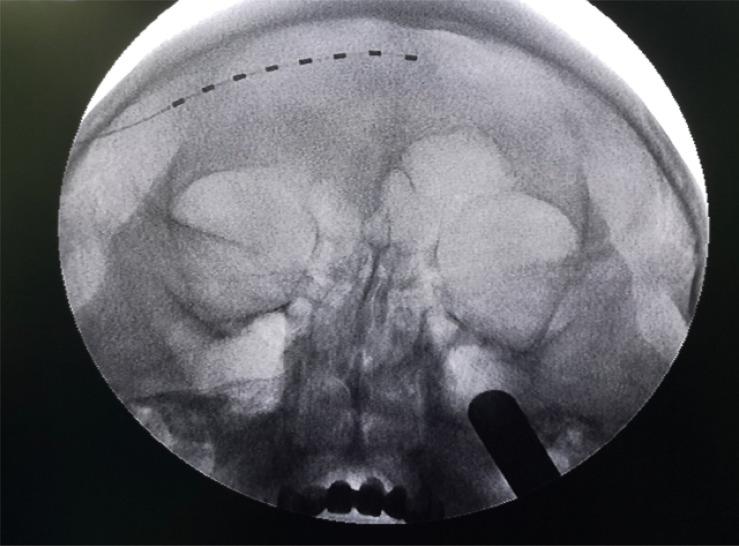

Peripheral nerve stimulation may be an alternative option to treat severe facial pain. We assessed the application of peripheral nerve stimulation for pain management in patients with herpes zoster ophthalmicus.

METHOD

A retrospective analysis was conducted in patients suffering severe facial pain caused by ophthalmic herpetic lesions. We identified the change in pain severity before and after peripheral nerve stimulation for up to 12 months.